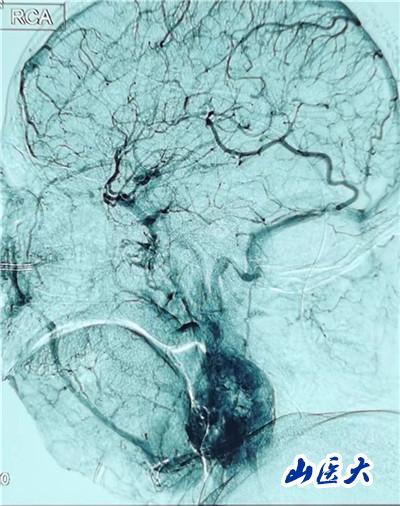

患者入院后,醫院成立了由口腔頜面外科、神經外科、血管外科、介入科、麻醉科、手術室組成的多學科團隊,對患者的病情進行反復研究,對手術方案進行多次探討。先由介入科楊敏玲主任醫師團隊對患者實施了頸動脈血管造影術,對腫瘤的血供情況進行詳細掌握;神經外科郭庚主任醫師團隊術前對患者進行了頸內動脈暫時性球囊阻斷試驗,對患者的腦缺血耐受性進行了科學評估。由醫務處牽頭又進行了全院大會診,制定了多套手術方案并對手術流程進行了反復梳理,準備了頸動脈修補—頸動脈人工血管重建—頸動脈覆膜支架置入等該領域最新技術手段。

手術在一體化復合手術室進行,付秀榮護士長安排了王超、霍夏楠、杜洋三位既熟悉口腔手術又了解介入操作的青年骨干配合,由麻醉科呂潔萍主任醫師團隊保駕護航,專門派具有20余年工作經驗的那江副主任醫師全程監護。因腫瘤體積較大,南欣榮主任團隊采用頸部橫切口入路顯露腫瘤,仔細解剖、小心保護舌下神經、迷走神經、副神經、頸內靜脈等重要結構,血管外科王貴明主任醫師團隊做好頸內動脈破裂修補準備,郭庚主任醫師團隊已完善了頸內動脈覆膜支架置入相關準備工作,若萬一出現血管破裂、修補困難等情況,即可立即啟動相關預案。順利的是,經過3個多小時精細解剖,暫時性阻斷頸外動脈近心端供血,在頸內動脈和頸外動脈均沒有破裂的情況下完整切除了腫瘤,手術獲得圓滿成功。